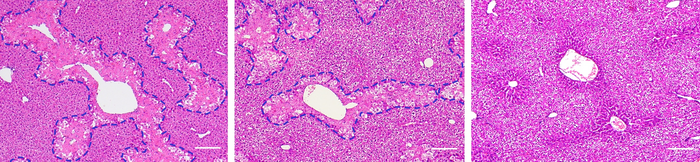

Variations of the formula for the synthesis of CoQ 10 -MITO-Porter were tested, and their structures were examined with electron microscopy. CoQ 10 -MITO-Porter was administered to mice models with acetaminophen-induced liver damage. Acetaminophen overdoses cause excess ROS in mitochondria, which in turn damages cells in the liver. CoQ 10 -MITO-Porter was transported primarily to the liver and measurably reduced the damage caused by ROS. A further discovery was that downsized CoQ 10 -MITO-Porter particles with more efficient packaging of CoQ 10 were more effective at treating liver damage than the original formulation.